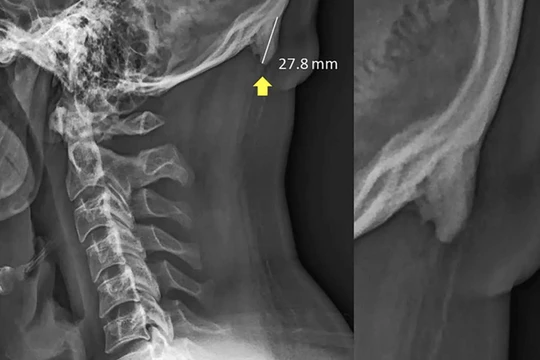

GS. Peter Martinez Benitez– Trưởng nhóm chuyên gia - trực tiếp thực hiện ca mổ